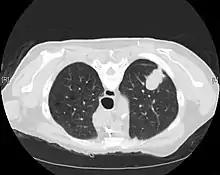

CT scan- adenocarcinoma of the left lung

The majority of lung cancers can be characterized as either small cell lung cancer (SCLC) or non-small cell lung cancer (NSCLC). Lung adenocarcinoma is one of the three major subtypes of NSCLC, which also include squamous carcinoma and large cell carcinoma.[15]